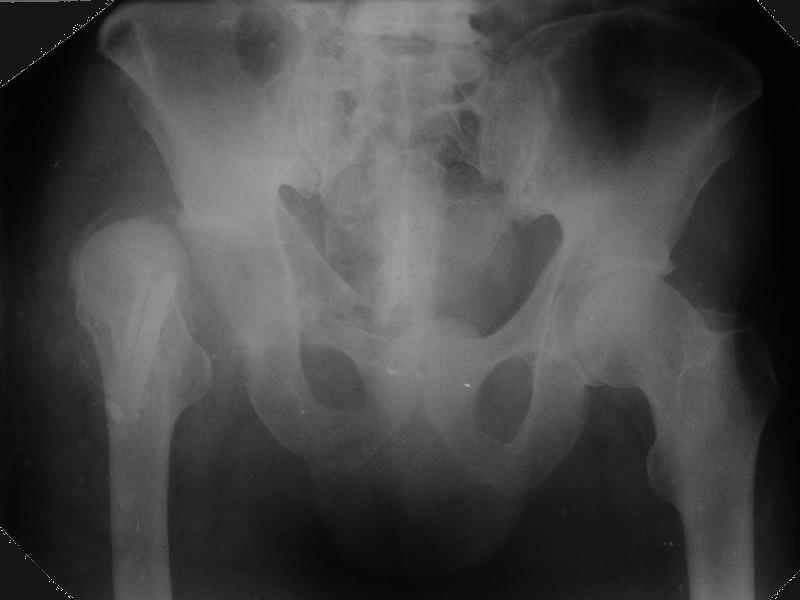

Уважаемые коллеги,Мужчина 1952 г.р. поступил в 36 больницу Екатеринбурга 1 июня 2004 г. Диагноз: Множественный перелом ребер слева, субтотальный гемоторакс, оскольчатый перелом шейки правого бедра.Повреждение таза не диагностировано. 17 июня 2004 г. - открытый остеосинтеза шейки бедра винтами с костной аутопластикой. Заживление раны первичное. Выписан 1 июля. 4 июля отметил укорочение конечности. При контрольном осмотре через 1 месяц после остеосинтеза - передний вывих бедра. Неправильно срастающийся перелом костей таза.Вопрос - особенности эндопртезирования тазобедренного сустава в этой ситуации?

Перелом там от бокового сжания, похоже на LC-I, т.е. компрессионный перелом крестца и на этой же стороне лонной и седалищной. Впадина выглядит совершенно целой. Если там и есть какая-то импрессия в переднем отделе - то микроскопическая.

По видимому снимки н/к сделаны в положении наружной ротации 90гр. И если даже так, то можно определить, что после выполненного остеосинтеза, шейка бедра практически отсутствует.

Даже при нормальной, не поврежденной впадине такое расположение головки относительно большого вертела обречено на вывих (теоретическое или биомеханическое обоснование можно найти в работах Рагозина А.О.).